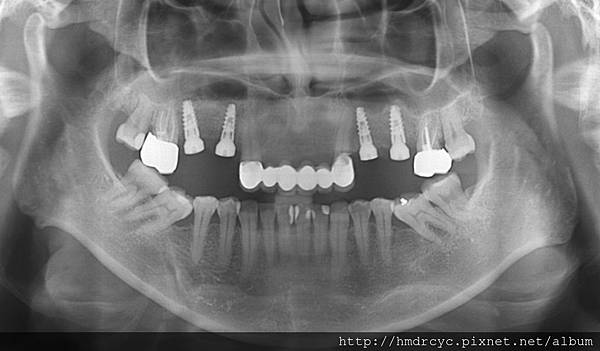

[人工植牙] 我的植牙好多年了 老植牙怎麼辦? 人工植牙推薦 高雄牙醫推薦

當代的植牙技術跟過去相比進步很多

都讓現在的植牙成果較十年前更可靠

所以就算是多年前的植牙

只要使用上沒有問題還可以用

其實不需要直接換掉

當然還是建議讓專業的植牙醫師評估

是不是真的沒問題囉